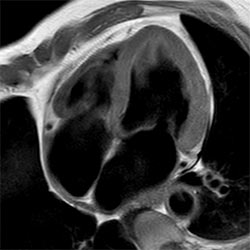

In a society where reimbursements are declining and chronic conditions lead to increased MR procedures and longer waiting times, there is ever increasing pressure on the radiology department. Today, further attempts to accelerate, compromise image quality or are limited to a narrow range of scans. Therefore, to meet the increased demand for productivity, a technology break-through in acceleration is still required. Leveraging our long standing leadership position in speed (i.e. SENSE), Philips brings compressed SENSE, a breakthrough in productivity.

Learn more about the main principles of Compressed SENSE and how it introduces a paradigm shift in productivity, how Compressed SENSE was designed around image quality, and how it advances productivity for clinical MR imaging.

Read about the experiences from Kantonsspital Winterthur (Switzerland) who experienced Compressed SENSE to be a simple yet powerful way to accelerate MRI scanning for different contrast types and sequences, in 2D as well as 3D.